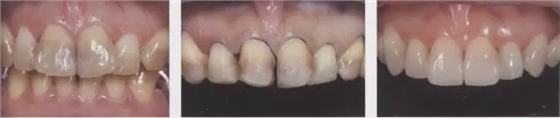

1、嵌體和高嵌體 在磨牙區(qū)域,由于牙齒近中面以及遠(yuǎn)中面的傾斜程度不同,常會遇到分離困難的病例。例如,智齒的近中根傾斜,引起鄰牙根間隙過窄的情況。相鄰牙齒的近中傾斜,牙冠進(jìn)入被處理牙倒凹處的情況(圖2、3)。以上情況,鄰接面由于齲齒形成窩洞,即便是運(yùn)氣好在齦下做了分離,也會因為出血造成取模困難、頰舌的成形變大。所以采取以下處理措施。 1、術(shù)前拍攝牙片,根據(jù)牙根的傾斜判斷有沒有引起鄰牙根間隙過窄的情況。若沒有傾斜,就是簡單病例。 2、若智齒沒有對合牙,也考慮拔除智齒。 3、鄰接面用樹脂填充之后,用間接法進(jìn)行烤瓷嵌體或烤瓷高嵌體修復(fù)。 1、貼面治療 對于變色牙齒進(jìn)行貼面治療的情況下,牙頸部觀察無變色的情況下,可直接在齦上做成形。普通成形深度能夠保存牙釉質(zhì),因而判斷為簡單病例。(圖4) 如果牙頸出現(xiàn)變色,就需要進(jìn)行齦下成形,難度增加。如果也存在前突問題,為改善變色貼面不能做厚,因而難度會更高。如果希望糾正前突、改善變色,則需要增加切削量,甚至可能進(jìn)行拔髓。另外,由于粘接對象主要是牙本質(zhì),因而需要格外注意。

圖4牙頸部無變色病例。雖然變色很嚴(yán)重但由于未延伸到牙頸部(左圖),可進(jìn)行齦上成形(中),最終調(diào)整到了很自然的顏色。(右)

圖5牙頸部變色的病例。貼面發(fā)生脫離,并有前突(上圖)。去除貼面后,整體變色明顯,因而進(jìn)行齦下成形,并做了1mm以上的切削。左1要進(jìn)行拔髓(下左)。由于粘結(jié)對象大部分為牙本質(zhì),取模前先進(jìn)行牙本質(zhì)染色,后做全瓷貼面試戴(下右)。